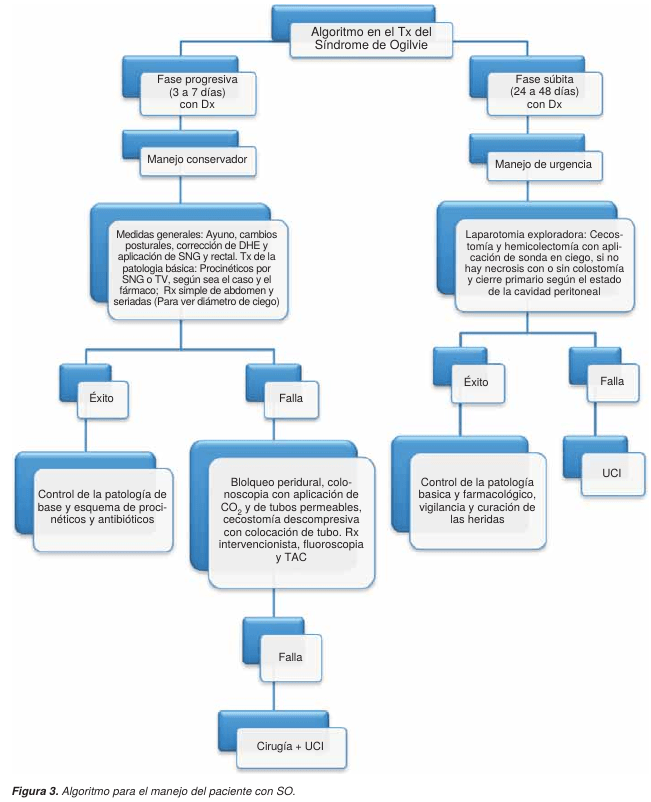

TRATAMIENTO

El tratamiento médico general del SO comprende diversas alternativas terapéuticas (Figura 3), desde medidas generales poco invasivas hasta la utilización de la descompresión colónica por colonoscopia y cirugía. Frecuentemente se inicia con ayuno (reposo intestinal), sonda nasogástrica y rectal, enemas evacuantes, cambios posturales, tratamiento de la enfermedad de origen, reposición hidroelectrolítica y supresión de drogas potencialmente implicadas en el desarrollo del síndrome.9,10-15 El tratamiento farmacológico más recomendado actualmente en SO es para corregir el desequilibrio del sistema autónomo de la motilidad colónica,5,10-12,16,19 basados en este hecho, se han utilizado actualmente la cinitaprida, la mesaprida y la itoprida,34 por su acción procinética sobre el colon, y su potente acción selectiva sobre los receptores 5-HT4, 5-HT2 y D2 produciendo liberación de acetilcolina en los plexos mientéricos (Cuadro IV).

La utilización de naloxona, un antagonista opioide está justifi cada en pacientes que han recibido analgésicos opiáceos. La anestesia epidural con bupivacaína16 se sustenta teóricamente en que el bloqueo simpático esplácnico aumenta el tono y la motilidad colónica. También se ha empleado el tratamiento combinado de bloqueo gangliónico con guanetidina seguido de estimulación colinérgica usando neostigmina con resultados positivos.23,24 Hay reportes de pacientes tratados con prostaglandinas con buenos resultados.22 La eritromicina un antibiótico macrólido agonista de la motilina con efecto sobre el músculo liso gastrointestinal, se ha usado en forma limitada en este síndrome.

CONCLUSIONES

El tratamiento farmacológico de series reportadas en la literatura con múltiples esquemas, donde se ha llehic.org.mx gado a establecer recomendaciones para la realización de estudios randomizados, controlados no sesgados para conocer el riesgo/beneficio de cada paciente. La descompresión colónica endoscópica fue introducida en 1977 por Kukora y Dent,33 publicaron una serie de seis pacientes con SO que fueron tratados con descompresión del colon utilizando un endoscopio, en cinco de seis pacientes el procedimiento fue exitoso, dando lugar a que la colonoscopia, se convirtiera en uno de los procedimientos más utilizados en el manejo de estos pacientes; con la única contraindicación, en los casos de isquemia de la mucosa y peritonitis. La limpieza mínima Este del colon documento en ciertos es elaborado casos con 1,000 por Medigraphic mL de solución jabonosa con el objeto de diluir las heces y puedan ser aspiradas fácilmente, el procedimiento debe hacerse insuflando una cantidad mínima de aire a las asas intestinales, para evitar una perforación; últimamente se ha utilizado el CO2 que se absorbe rápidamente, tiene un efecto vasodilatador y disminuye la posibilidad de isquemia y perforación.

Sin embargo, siempre existe la posibilidad de una perforación.5,17,18-27 Debido a las recidivas con la colonoscopia descompresiva, se han propuesto varias modificaciones al procedimiento: 1) la colonoscopia con doble canal de trabajo y colocación del tubo de drenaje fenestrado que se introduce utilizando las pinzas de biopsia o el asa de polipectomía;25 2) colonoscopia con canal de trabajo único y colocación de guía cubierta por teflón con paso posterior de un tubo fenestrado a través de la guía, y 3) colonoscopia con un sobretubo fenestrado.17 En la técnica de descompresión colonoscópica con tubo de drenaje, lo ideal es dejar el catéter en ciego, sin embargo, este objetivo es un reto para el endoscopista debido a que se realiza el procedimiento en un colon no preparado y en un paciente habitualmente grave. Otra alternativa reciente es usar un stent de metal expandible para la obstrucción no complicada.33 También se ha demostrado que la sonda de drenaje colocada en el sitio proximal al ángulo esplénico ofrece iguales resultados terapéuticos.30 La recomendación de la cirugía se basa en los cambios isquémicos en la pared cecal que inicia en la serosa y progresa a la mucosa, de tal forma que la presencia de isquemia de la mucosa debe interpretarse como una afección transmural con alto riesgo de perforación. La cirugía como se ha señalado anteriormente es necesaria después de la recidiva o complicación al efectuar la descompresión.

La cecostomía percutánea es un método eficaz descrito como alternativa de tratamiento en pacientes con SO. Este tratamiento se reserva para pacientes en quienes no fue posible practicar una colonoscopia descompresiva por dificultades técnicas o que no han mostrado mejoría después de ésta. Este procedimiento es realizado por un radiólogo intervencionista. Se utiliza un abordaje de tipo transperitoneal o retroperitoneal guiado por tomografía axial computada; 30,31 se ha sugerido que el abordaje retroperitoneal puede tener algunas ventajas, como la retención en el retroperitoneo del contenido cecal en caso de fuga, evitando la peritonitis; sin embargo, en los casos reportados en la literatura donde se ha utilizado un abordaje transperitoneal, la peritonitis no ha representado una complicación importante pero la presencia de heces en retroperitoneo puede causar una fascitis infecciosa. 20,29,32 Los estudios anatómicos en cadáveres sugieren que el abordaje retroperitoneal es muy difícil, esto debido a la extensión posterolateral del peritoneo y la sobreposición lateral y posterior del hueso iliaco.20 La cecostomía percutánea tiene la desventaja de que no precisa el grado de necrosis de la mucosa intestinal ni la presencia de perforaciones.

El sistema coaxial de tres componentes guiado por fluoroscopia es otra de las técnicas utilizadas por los radiólogos para el manejo del SO. Este procedimiento surgió de la idea que la falla de los tubos rectales se debía a que éstos eran muy cortos. Este sistema es una modificación del catéter tradicional coaxial angiográfico. Incluye un catéter rectocolónico externo, un catéter guiado interno y una guía central de alambre central, que se introduce a través del recto y con el uso de fluoroscopia puede ser guiado hasta el colon proximal, este método también tiene sus limitantes y al final no valora el estado de isquemia de la mucosa y su principal complicación es la hemorragia y perforación.25

Tratamiento quirúrgico para el SO. Las modalidades son: cecostomía descompresiva, colectomía y/o colostomía, consisten en efectuar una laparotomía exploradora con objeto de evaluar las condiciones y complicaciones del colon (isquemia, necrosis, perforación, abscesos y peritonitis). Cuando el colon no tiene datos de isquemia o perforación, el procedimiento de elección es la colocación de un tubo de cecostomía. Cuando el estado del colon demuestra un grado importante de isquemia, necrosis y perforación la resección colónica será la propuesta y el cirujano decidirá de acuerdo a su experiencia y al estado de la cavidad peritoneal, si el cierre es primario con o sin protección de una colostomía. La laparoscopia como método de diagnóstico y tratamiento en pacientes con SO, valora el grado de visibilidad y de lesión del intestino. Si durante la laparoscopia se encuentra un ciego con necrosis extensa, se realiza laparotomía y resección intestinal. Si los cambios de isquemia son mínimos, se coloca una sonda en ciego o se realiza la cecostomía por laparoscopia, lo que evita las complicaciones de la cirugía convencional.26

Las recidivas del SO en pacientes tratados por cirugía es prácticamente «nula»,28 sin embargo la morbimortalidad de los procedimiento con cecostomía, resección intestinal y/o colostomía oscila del 20 al 57%.12 La infección de la herida, hernia incisional, prolapso cecal con infarto y eventración son las complicaciones más frecuentes.12